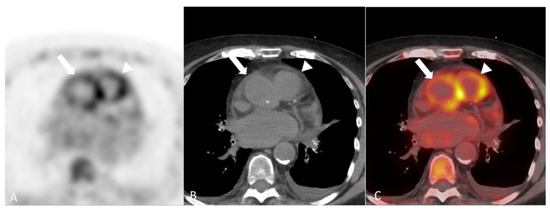

- Soussan, M.; Abisror, N.; Abad, S.; Nunes, H.; Terrier, B.; Pop, G.; Eder, V.; Valeyre, D.; Sberro-Soussan, R.; Guillevin, L.; et al. FDG-PET/CT in patients with ANCA-associated vasculitis: Case-series and literature review. Autoimmun. Rev. 2014, 13, 125–131. [Google Scholar] [CrossRef]

- Kemna, M.J.; Vandergheynst, F.; Voo, S.; Blocklet, D.; Nguyen, T.; Timmermans, S.; van Paassen, P.; Cogan, E.; van Kroonenburgh, M.; Tervaert, J.W.C. Positron emission tomography scanning in anti-neutrophil cytoplasmic antibodies-associated vasculitis. Medicine 2015, 94, e747. [Google Scholar] [CrossRef] [PubMed]